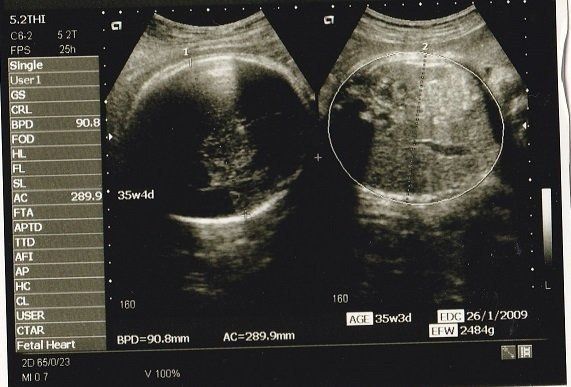

妊娠35週目のエコー写真 いよいよ出産へ

妊娠9カ月になり、いよいよ出産に向けての準備段階です。母親学級に参加して、出産についていろいろと勉強しました。待望のわが子に会えるまで、あと少しです!

私の息子は生まれたときから髪がふさふさでした。このころから髪が伸びていたのかな?